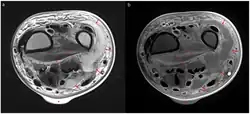

Magnetic resonance imaging (MRI)

Axial T2 weighted MRI (a) and contrast-enhanced MRI (b) of left wrist showing necrotizing fasciitis. There is diffuse hyperintensity with irregular enhancement of the deep fascia (asterisks). The arrows indicate a lobulating abscess, and the triangle a skin bulla.

Magnetic resonance imaging (MRI) is considered superior to computed tomography (CT) in the visualization of soft tissues and is able to detect about 93% of NF cases.[15] It is especially useful in finding fluid in the deep fascia, which can distinguish between NF and cellulitis.[15] When fluid collects in the deep fascia, or thickening or enhancement with contrast, necrotizing fasciitis should be strongly suspected. However, MRI is much slower than CT and not as widely available.[15] There may also be limitations on its use in patients with kidney problems.[15]